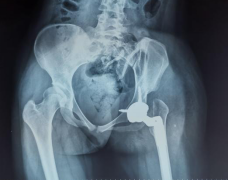

通过术前充分的准备,小张的手术也如约而至。当天在术中,毕郑刚和耿硕发现小张的患侧股骨头和髋臼都存在发育异常,没有软骨而且形状较不规则,难以契合,保髋方案不可取,于是只能采取方案二:全髋关节置换术。因为术前提前进行了规划,相应型号的假体也已经提前准备,髋臼假体及股骨假体安装得较为顺利。然而和预料的一样,在髋关节假体尝试复位时软组织张力较大,很难进行复位。因为在术前患侧股骨通过极限力量牵引验证了不截骨复位的可能性是存在的,为了能够让患者一期恢复腿长,避免二次手术,毕郑刚和耿硕决定通过进行软组织的松解来复位,选择了不进行股骨截骨,但是考验手术技术。经过对髋关节周围软组织的松解后,最终假体复位成功,随后通过比对双下肢长度,提示等长,关节活动度良好,宣告手术一期顺利完成。术后小张返回病房,因为未进行截骨仍有软组织张力大致神经血管等损伤的风险,术后嘱其行患肢适度屈髋屈膝位来减缓软组织张力,2~3周内逐渐伸直。术后通过查体,小张并未出现神经的损伤症状,手术成功。

(术后X线)